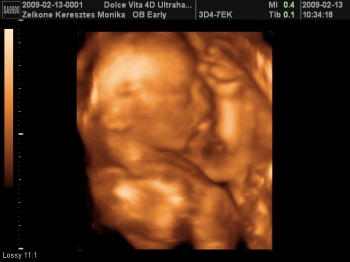

Az 1. Női Klinikán voltam szívuh-n.